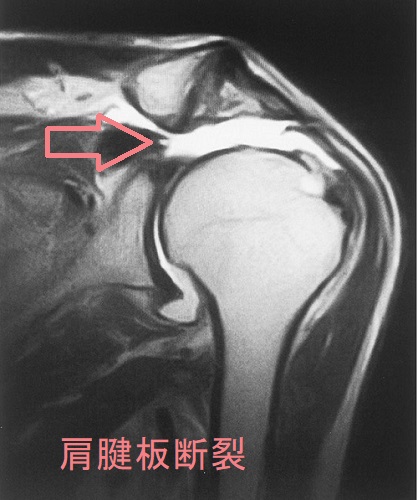

中高年に好発する肩腱板断裂は、重いものを持ち上げた時などに発症。突然の肩痛で始まり、最初は動作時の痛み(動作時痛)、次第に安静時痛と夜間痛も出現します。ある一定の肢位で疼痛が増強する有痛弧徴候、その肢位を保持できない腕落下徴候を認めます。

近年、肩腱板断裂の発生率が増加しています。当然ながら、肩腱板腱には甲状腺ホルモン受容体が存在し、腱の代謝と維持に関与しています。肩腱板断裂で関節鏡手術や小開放手術を受けた患者は、男女ともに高頻度で甲状腺疾患を持っていたとする報告があります。(Muscles Ligaments Tendons J. 2014 Nov 17;4(3):309-14.)